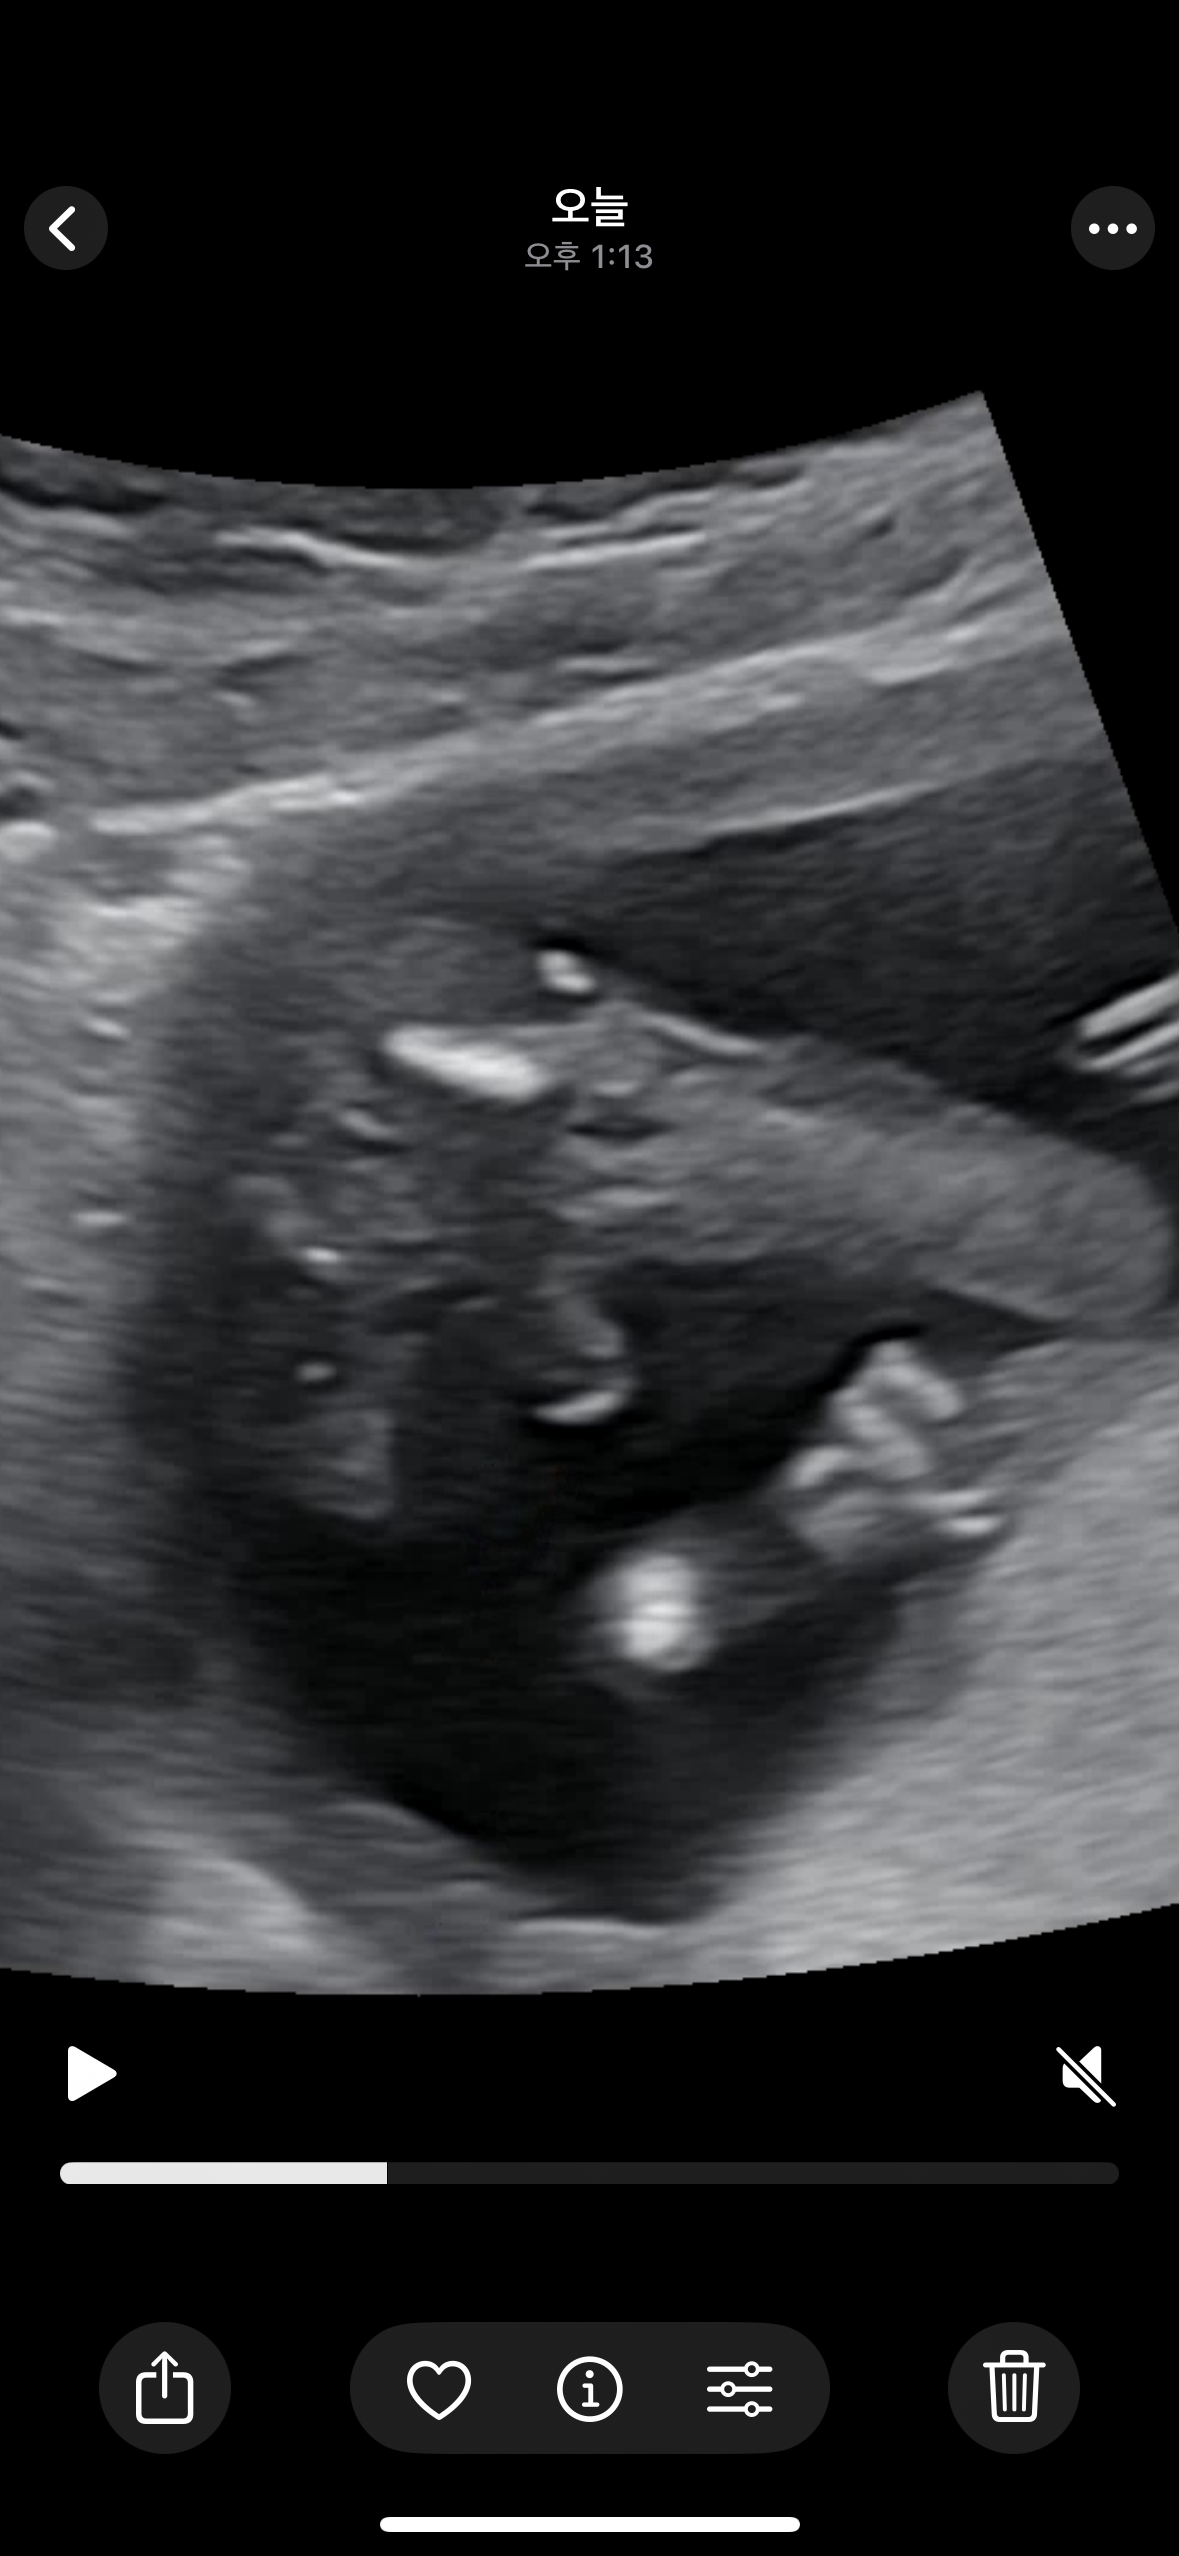

15주 4일입니다!!

튀어나와 있긴 하지만 첫째때랑은 좀 달라보여서요! 첫째가 아들인데 첫째땐 완전히 삼각점이 였거든요…! 약간 꼬깔콘 마냥?? 비교사진 올리고 싶은데 사진이 한 장 밖에 안올라가나봐요ㅠㅠ